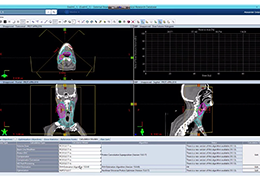

ART-Plan™ Artificial Intelligence Contouring